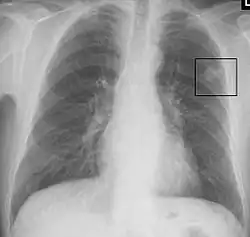

Radiografía simple de tórax

Radiografía de tórax mostrando un tumor canceroso en el pulmón izquierdo (en el recuadro).

En las radiografías simples de tórax se puede observar alguna anormalidad en casi el 98 % de los pacientes con un carcinoma broncogénico, y el 85 % son imágenes sugestivas para sospechar el diagnóstico por las alteraciones pulmonares distales (atelectasia), la existencia de adenopatías (ensanchamiento mediastínico) o detección de invasión de la pared torácica. La radiografía de tórax detecta elementos sospechosos en la mayoría de los pacientes con tumores pulmonares.[133]​ No se recomiendan las tomas radiológicas en serie para la detección temprana del cáncer de pulmón.[121]